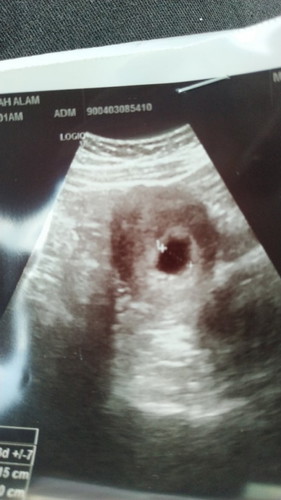

Dah 10 minggu pergi scan doctor tunjuk kantung je, normal ke?

Harini pergi scan, doctor cakap nampak kantung je dia tnya tarikh last period tu betul x, sy ckp betul sebab tiap2 bln ada rekod, so lagi 2 minggu dtg scan lagi. Benda ni normal ke? Risau plak saya.

Hi sis, saya pun macam ni jugak dah 8 minggu tapi nampak kantung je, size kantung tu kecik je rupanya baru 5minggu. InshaAllah kandungan sihat selagi takde pendarahan.